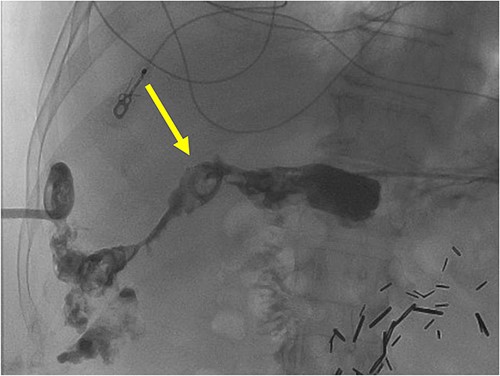

A radiographic fistulogram demonstrating the fistulous tract communicating with the second part of the duodenum.

A radiographic fistulogram demonstrating the fistulous tract communicating with the proximal duodenum/gastric pylorus.